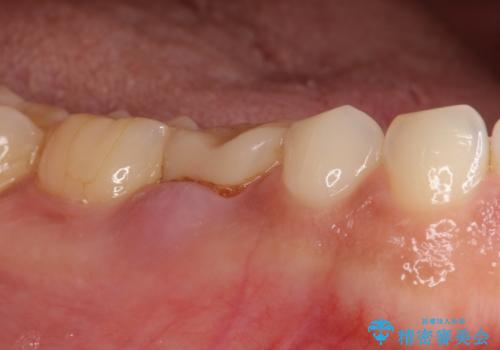

[20代男性] インプラント 失った歯の治療

![[20代男性] インプラント 失った歯の治療の症例 治療前](https://seimitsushinbi.jp/wp/wp-content/uploads/2019/11/IMG_0002-6-500x350.jpg?v=1574736384)